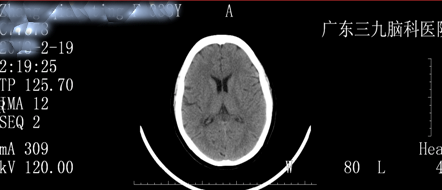

8:20(次日)复查头颅CT平扫未见异常。(图四)

图四:治疗后头颅CT